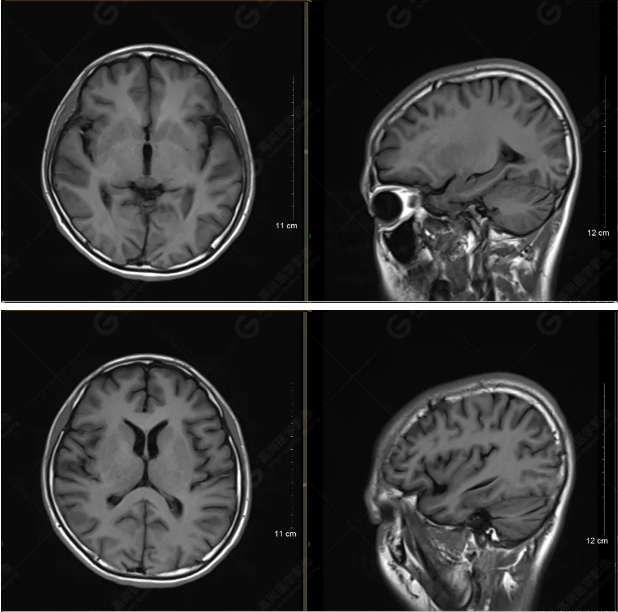

以下是T1WI軸位掃描及矢狀位掃描:

雙側(cè)大腦半球?qū)ΨQ,灰白質(zhì)對比正常,顱內(nèi)未見異常信號影。腦室系統(tǒng)未見擴(kuò)大,中線結(jié)構(gòu)居中。腦溝、裂未見增寬。幕下小腦、腦干未見異常。矢狀位示垂體形態(tài)、大小級信號未見異常。所示左側(cè)乳突內(nèi)見多發(fā)短T1長T2信號影。

顱腦MRI平掃未見明顯異常,左側(cè)乳突內(nèi)積血,建議補(bǔ)充SWI檢查。(左側(cè)為薄層原始圖像,右側(cè)為后處理5mm圖像)